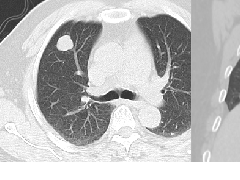

1、CT表现:平扫期可见肝实质性肿块,边缘清楚或不清,内可见多发散在更低密度区,肿瘤常突入腹腔,内可见钙化灶;增强期可见多个结节状增强染色征象,病灶周围呈结节状、片状明显强化,密度高于肝脏,门脉期呈低密度。

1、假包膜:肝母细胞瘤通常现为巨大的单一肿块,少数为多结节融合。大部分边界清楚, 假包膜形成,病理上为周边受压的正常肝组织。一般胎儿型的包膜较完整, 而胚胎型的欠完整。

2、裂隙征:裂隙或不规则更低密度区代表肿瘤的坏死区;

3、钙化:小斑点状或条状钙化,主要见于混合型肝母细胞瘤,病理上钙化由瘤内的骨样组织有关.

4、分隔样强化区:肿瘤内血窦有丰富的胶原纤维分隔 以及静脉参与有关,造影剂较多存留在胶原纤维的血窦内而在延时明显强化 。

5、肿瘤血管征:可见较多粗细不一的肿瘤血管。肿瘤以外肝实质一般无明显异常,瘤周可见受压弯曲的肝血管影,主要为肝静脉和门静脉。